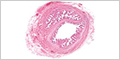

MH 146 Ureter

Chapter 16 - Urinary System

MH 147 Bladder

Chapter 16 - Urinary System

MHS 214 Bladder

Chapter 16 - Urinary System